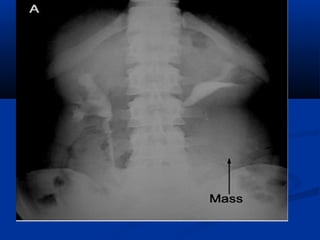

Plain X-Plain X-

Ray:Ray:

Large soft tissue massLarge soft tissue mass

displacing bowel gasdisplacing bowel gas

Calcification is uncommon.Calcification is uncommon.